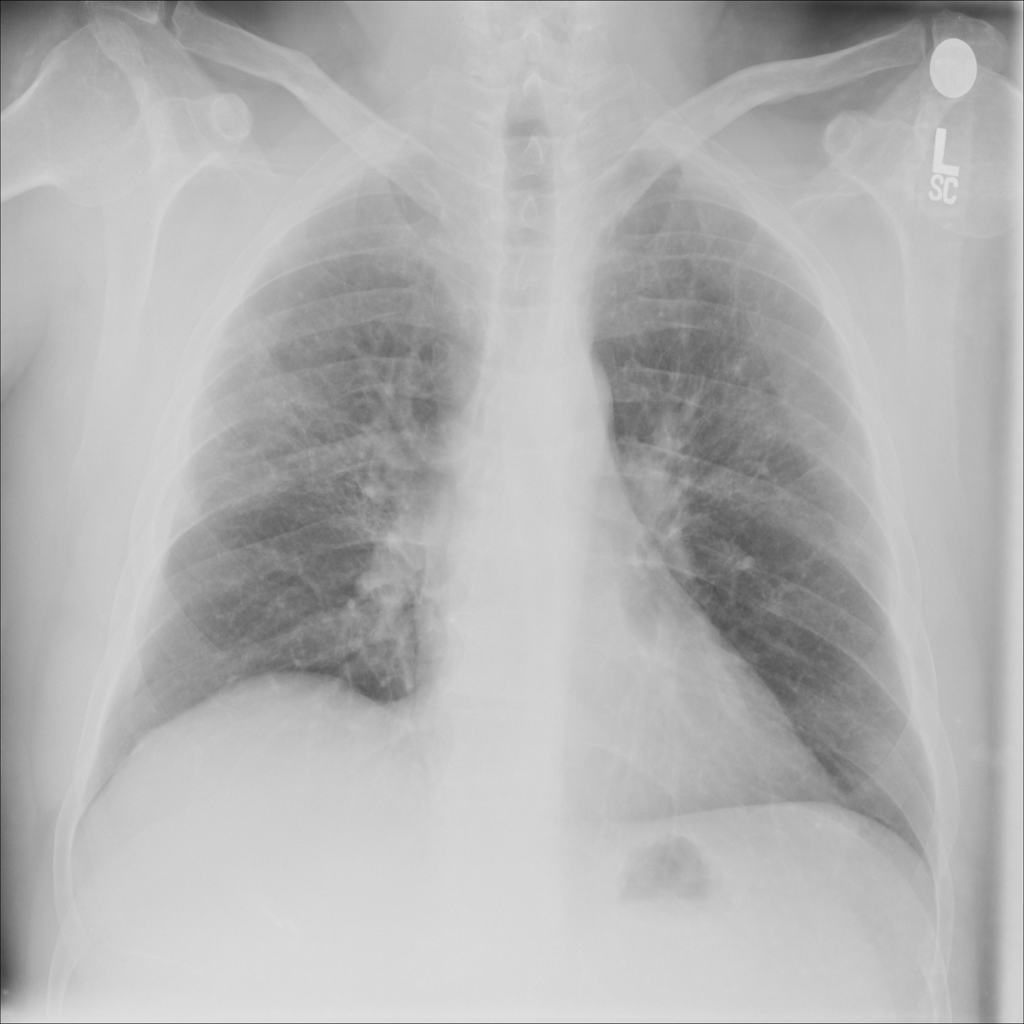

PAT-C255 · IMG-000Emphysema

PAT-C255 · IMG-000

PA